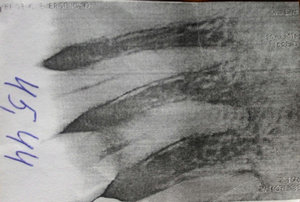

Добрый день. Мне в стоматологии сделали снимок зуба и сказали, что зуб надо удалять, так как вылечить не получится. Подскажите, так ли это? Может стоит обратиться к другим врачам? (фото зуба выслала на e-mail). Зуб № 46. На данный момент зуб не беспокоит. Три месяца назад был флюс, после разреза всё прошло. Антибиотиками не лечила, так как беременность. Сейчас срок 17 недель. Спасибо!

Да, к сожалению зуб необходимо удалить, так как на верхушках всех корней наблюдается обширное воспаление.